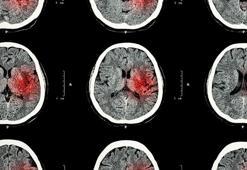

Ani baş dönmesi felç işareti olabilir! 55 yaş üstünü özellikle uyardıBeynin bir bölümüne iletilen kan akışının azaldığı ya da kesintiye uğradığı durumlarda felç kendini gösteriyor. Özellikle 55 yaş üstünü tehdit eden bu tehlike hakkında bilgi veren Nöroloji Uzmanı Dr. Hikmet Dolu, merak edilenleri anlattı.

Pandemide inme belirtilerine rağmen hastalar doktora gitmedi!Hacettepe Üniversitesi Nöroloji Yoğun Bakımı Ana Bilim Dalı Başkanı Prof. Dr. Mehmet Akif Topçuoğlu, Covid-19 pandemi döneminde inme belirtileri görülmesine rağmen hastaneye gitmekte tereddüt eden hastalar olduğunu söyledi. Prof. Dr. Topçuoğlu, "Eğer yüzde kayma, kolda kuvvetsizlik ve konuşma bozukluğu varsa inme geçiriyor olabilirsiniz ve 112yi aramanız gerekli. Akut inmenin tedavisi vardır ama bu tedavi belirli süre içindedir" dedi.

İnme Nedir? İnme (Felcin) Belirtileri Nelerdir, Tedavisi Nasıl Yapılır?İnme, beyne giden hayati oksijen ve kan akışının ani bir şekilde kesilmesi ya da azalması sonucunda oluşan beyin krizine verilen isimdir. Kan akışının hızlı bir şekilde kesilmesi sonucunda hücreler hızlı bir şekilde ölmeye başlar ve inmenin meydana geldiği bölgede fonksiyon kaybında geçici ya da kalıcı hasar meydana gelebilir. İnme nedir ve İnme belirtileri nelerdir? İşte, tüm detaylar.